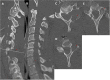

Figure 3. Postoperative MRI after the initial surgery

Postoperative contrasted sagittal and axial MRI after the initial surgery shows a subtotal resection with residual tumor (red arrows) at the facet and near the left vertebral artery MRI: magnetic resonance imaging

Figure 5

Figure 5. Postoperative MRI after the second surgery

Postoperative contrasted MRI sagittal and axial after the second operation demonstrating gross total resection of the tumor MRI: magnetic resonance imaging